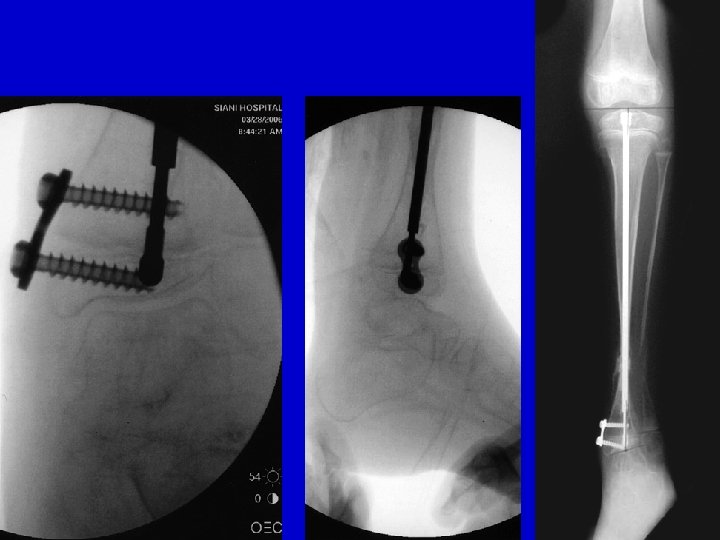

Type I Treatment Lateral AP

preop postop

Flexible IM nail 3 year follow-up

Fassier-Duval Telescopic Nail

LLD